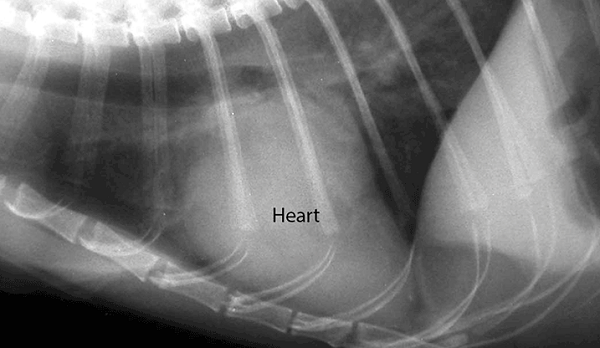

Nếu chó hoặc mèo của bạn có bất kỳ triệu chứng nào của bệnh tim, điều quan trọng là phải đưa ngay đến các cơ sở thú y để được khám. Các bác sĩ thú y sẽ có nhiều khả năng xác định các dấu hiệu của bệnh tim hơn bằng cách thực hiện một cuộc kiểm tra hoặc chụp X quang.

Bác sĩ thú y có thể nghi ngờ chó mèo bị bệnh tim nếu quá trình khám sức khỏe của chó mèo cho thấy sự thay đổi màu mô nướu, rối loạn tĩnh mạch, nhịp tim không đều, huyết áp cao và / hoặc nhịp tim hoặc âm thanh không đều. thậm chí. Nếu phát hiện thấy bất thường, xét nghiệm máu, chụp X quang, điện tâm đồ và / hoặc siêu âm tim thường được khuyến cáo để chẩn đoán.